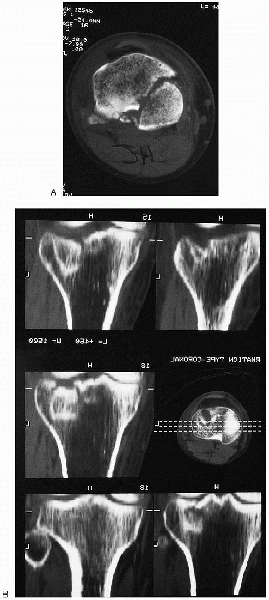

are useful for the preoperative plan. Tri-spiral and computed

tomography coupled with sagittal reconstructions are helpful in

evaluating the degree of articular displacement

(Fig. 30-4).

These studies are an excellent adjunct to plain x-ray films in the

preoperative planning for lag screw placement, particularly when

contemplating percutaneous fixation. Magnetic resonance imaging may

FIGURE 30-4. Computed tomographic scan (A) and sagittal reconstruction (B) of a tibial plateau fracture.